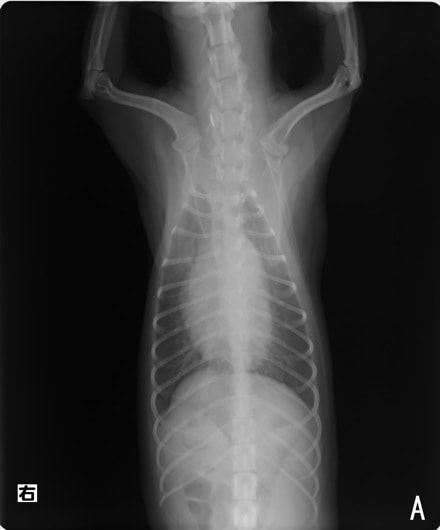

症例:【マルチーズ 12歳齢 去勢オス】

D:胸部レントゲン写真 正面像

左側胸壁心尖部領域を最強点とするLevine 5/6の収縮期性心雑音が聴取された。

胸部レントゲン検査において重度の心拡大と肺水腫が認められた。超音波検査では、重度の僧帽弁閉鎖不全症、三尖弁閉鎖不全症、中程度の大動脈弁閉鎖不全症を合併していることが判明した。三尖弁逆流速度から肺高血圧症が示唆された。

ACE阻害薬、ピモベンダン、硝酸イソソルビド徐放剤、ベラプロストナトリウム、利尿剤としてフロセミドとスピロノラクトンを用いて治療を行った。